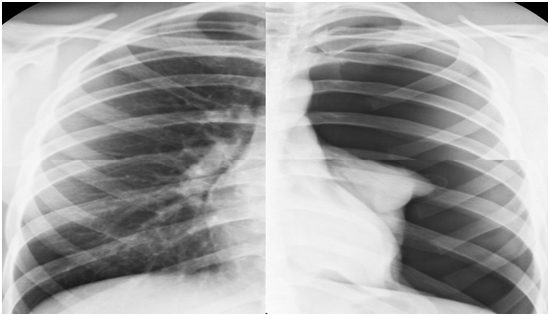

Transtorakal exokardioqrafiya müayinəsi zamanı döş qəfəsində heç bir deformasiya olmadığı halda parasternal görüntülər yalnız sağ körpücükaltı nahiyədən əldə oluna bilmişdir. Sol mədəcik funksiyaları normal olub, qalxan aortada patologiya aşkarlanmamışdır. Sağ mədəcik ölçüləri yüngül dərəcədə genişlənmiş (30mm) olub, soldan sağa şunt və ya mühüm qapaq patologiyası müşahidə olunmur. Döş qəfəsində deformasiya olmadığı halda parasternal görüntülərin sağ körpücükaltı nahiyədə alınması, EKQ-dəki dəyişikliklər döş qəfəsi daxili patologiyanın olmasına fikir verməyə əsas verir. Döş qəfəsinin rentgen müayinəsində sol tərəfli total pnevmoraks aşkarlandı (şəkil 2).

Şəkil 2. Döş qəfəsinin rentgenoqrafiyasında soltərəfli massiv pnevmotoraks izlənilir.